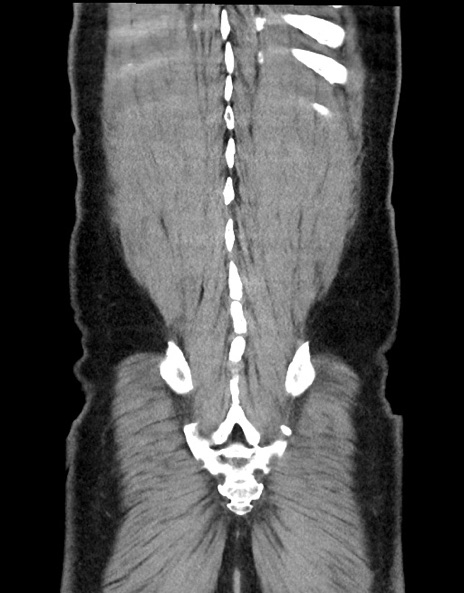

症例15(冠状断像)

【症例】70歳代男性

【現病歴】今朝から腹痛あり。全体的に痛い。特に左上の方。排ガスが今日はない。冷や汗が出る。

【既往歴】直腸癌術後